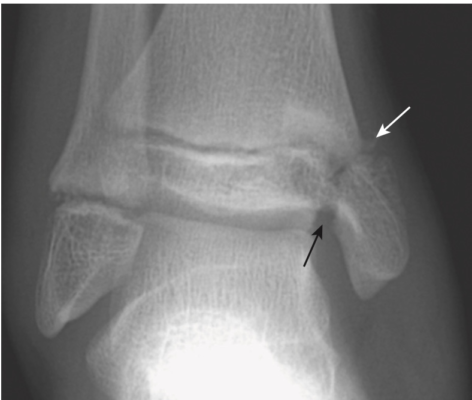

- Gãy Pouteau -Colles: gãy đầu dưới xương quay với đầu gãy di lệch gập góc mu tay, do ngã chống bàn tay (fall on the outstretched hand, FOOSH). Thường kèm theo gãy mỏm trâm trụ (ulnar styloid) (Hình 10).